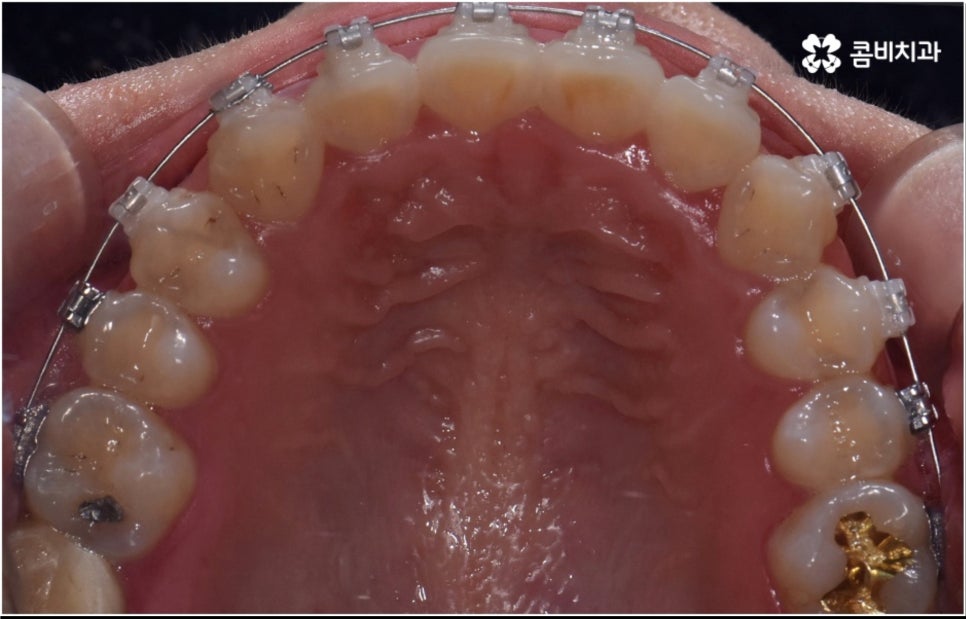

3D CT 등 정밀 검진 기계를 통해 꼼꼼하게 검진을 한 후 환자분들의 부정교합의 종류 및 정도 등에 따라 각자에게 맞는 교정 치료 계획을 수립하게 되는데, 내부 공간이 얼마나 있는지에 따라 발치가 필요한지 아닌지 여부도 달라지고 또 같은 부정교합이라고 해도 사람마다 잇몸 건강이나 치근 상태 등에 따라 잇몸뼈가 벌어지면서 치아가 이동하는 속도, 치아가 자리잡는 양상 등도 모두 달라지기 때문에 성인 치아교정 기간 총 소요 시간은 모두 달라질 수 밖에 없을 거예요.

물론 일반적으로 성장기보다는 잇몸뼈가 굳어진 이후 성인 치아교정 기간 이 길어질 수 밖에 없으나 이 역시 케이스별로 달라질 수 있어요. 예를 들어 만약 임플란트를 심으려고 할 때 공간이 없거나 주변 치열이 삐뚤어져서 어려움이 있기 때문에 하는 교정이거나 앞니 일부가 조금 벌어지고 살짝 각도가 앞으로 나와 있는 등 별다른 골격적 문제 없이 기능성 및 심미성을 보다 개선해 주기 위해서 하는 교정의 경우는 부분 교정으로 진행하기 때문에 보통 발치 과정도 포함되지 않고 성인 치아교정 기간 도 6~8개월 정도로 보다 빠르게 끝날 수 있습니다.

하지만 부정교합의 정도가 심하거나 골격적 문제를 바로잡아 주어야 하는 경우는 전체 교정을 진행해야 하기 때문에 (환자분들마다 다르지만) 평균적으로 18~36개월 정도의 성인 치아교정 기간 이 소요되며, 중장년 성인분들 중에 잇몸 질환 등으로 구강 건강이 약해져 있는 분들의 경우에는 더욱 환자분들의 상황에 맞게 필요한 치료를 병행하면서 무리하지 않은 진행을 해야 하기 때문에 전체 기간이 좀 더 늘어날 수 있어요.

치아 색상의 세라믹 브라켓을 이용하는 장치들은 예전 메탈 장치 보다 심미성이 훨씬 보완되었으며, 치아 뒤쪽에 장치를 부착하여 아예 눈에 띄지 않는 설측교정장치나 언뜻 보면 티가 잘 나지 않는 얇고 투명한 특수 강화 플라스틱을 이용하는 투명교정장치를 이용하면 교정을 하고 있다고 본인이 말을 하지 않으면 잘 모를 정도로 심미성이 뛰어나기 때문에 각 장치들의 소재와 특성, 장단점에 대해서 잘 알아보고 신중한 선택을 하는 것이 중요하다고 할 수 있어요.